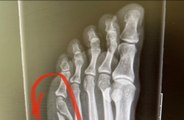

Coleen Rooney shares broken toe X-ray

Coleen Rooney shares broken toe X-ray after claims she was ‘milking’ court moon-boot